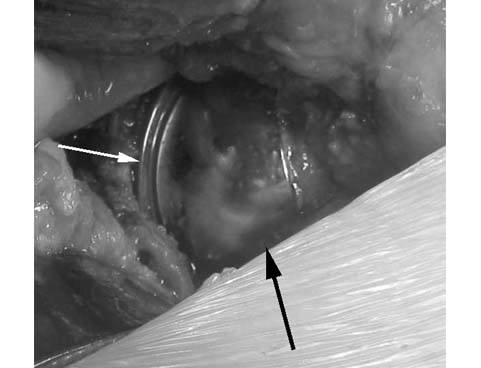

6.The femoral component is cemented into place. In the photograph, above the femoral (large black arrow) and acetabular components (small white arrow) are mated and the femoral head is placed within the socket. The range of motion is checked at this point in the surgery.